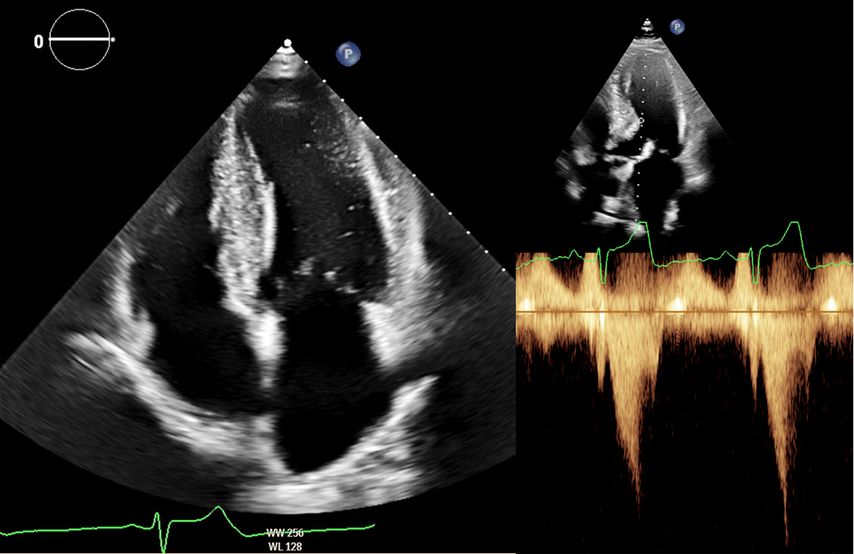

Zur echokardiografischen Beurteilung einer LVH wird üblicherweise der Durchmesser des intraventrikulären Septums und der Posterolateralwand herangezogen. Hier gelten bereits Werte >9mm bei Frauen und >10mm bei Männern als verdickt. Methodenbedingt werden die Wanddicken in der Echokardiografie jedoch häufig überschätzt (Abb.2). Definiert ist die LVH deshalb über die myokardiale Masse bezogen auf die Körperoberfläche (BSA; w: ≤95g/BSA; m: ≤115g/BSA), einen Parameter, der in der klinischen Praxis kaum verwendet wird.8

Abb. 2: Echokardiografie bei HOCM mit 4-Kammer-Blick (links) und Obstruktion im Ausflusstrakt (rechts)

Dennoch ist die Echokardiografie aufgrund der niederschwelligen Verfügbarkeit als erste Untersuchungsmodalität und zur Verlaufsbeurteilung nicht wegzudenken. Mit der Ejektionsfraktion, der Vorhofgröße und der Beurteilung der diastolischen Funktion können prognostisch wichtige Parameter erhoben werden. Ein „apical sparing“ in der Analyse des myokardialen Strains oder der Aspekt eines „granular sparkling“ kann einen Verdacht auf kardiale Amyloidose begründen (Abb.3). Jede echokardiografische Untersuchung wegen des Verdachts auf LVH sollte außerdem eine Bestimmung des LVOT-Gradienten inkl. Valsalva-Manöver beinhalten (Abb.2).